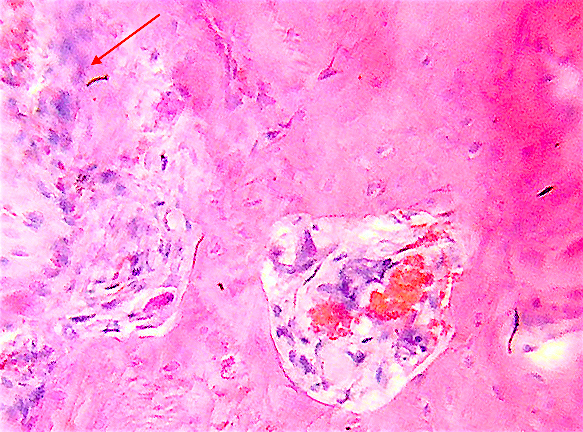

7. Келликер открыл остеокласт в 1870 году

Келликер открыл остеокласт в 1870 году; "они выгрызают кость и находят в углублениях".

Это Лакуны Хаушипа или ниши резорбции.

В остеокластах многно отдельных ядер 2-100 и больше.

У старых клеток есть также пикнотические ядра.